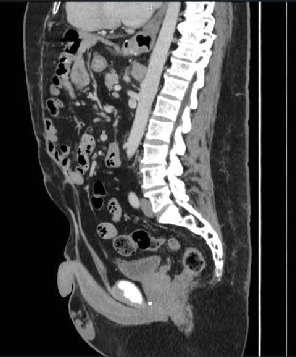

Abdominoplasty is a frequently performed elective procedure, often indicated for patients after substantial weight loss resulting in significant redundant skin. Closing techniques and the lifting of the mons pubis during abdominoplasty have been proposed to alleviate symptoms of stress urinary incontinence by elevating and supporting the urethra. Despite these observations, the impact of abdominoplasty on pelvic anatomy and subsequent endoscopic procedures remains underexplored and underreported. We present a case where cystoscope passage as part of endoscopic laser lithotripsy for nephrolithiasis was impeded by altered anatomy in a patient with a history of Fleur-de-Lis abdominoplasty.